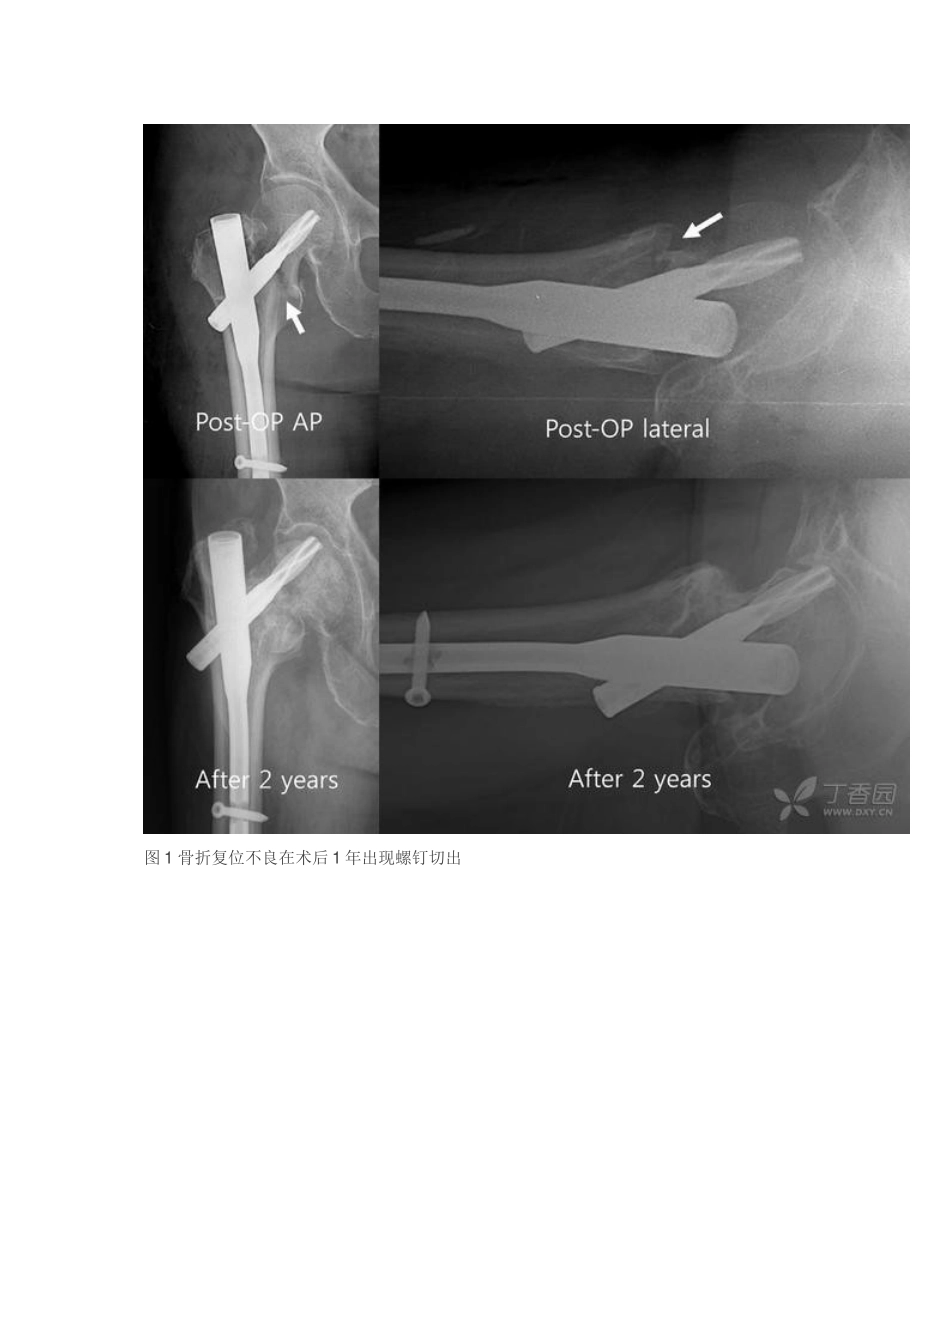

股骨转子间骨折骨钩撬拨复位技术股骨转子间骨折是髋部常见骨折,其中 75%的股骨转子间骨折为不稳定型骨折类型,髓内钉固定期目前内固定治疗股骨转子间骨折的一种治疗选择,但是假如术中骨折没有得到准确的解剖复位,术后也许会出现螺钉切除或断裂等严重并发症(图 1)。大多数的股骨转子间骨折通过纵向牵引并将远端肢体内旋就可取得较好的闭合复位效果,但是一些难以复位的骨折则需要经皮小切口辅助手术甚至需要做骨折端的切开复位。Carr 等人发现有一类股骨转子间骨折通常需要经皮操作才能取得解剖复位,这种骨折具有以下特点:骨折远端的股骨短缩并外旋,骨折近端的股骨头和股骨颈不仅存在内翻畸形并且向后移位进入粉碎的股骨转子间区域,骨折近端股骨颈前侧骨质和骨折远端股骨嵌插。对于这种骨折,通过闭合复位很容易取得正位片上解剖复位的效果,但是侧位透视时骨折端仍存在前侧骨皮质断裂分离需要调整复位(图 2)。为解决上述复位难题,韩国的 Youngwoo Kim 医生使用钩撬拨复位技术取得良好疗效,其经验发表在 2025 年 5 月的Injury 上。图 1 骨折复位不良在术后 1 年出现螺钉切出图 2 闭合复位后的股骨转子间骨折,在正位透视显示骨折复位良好(骨折移位少于 1 个皮质厚度,左侧图),但是侧位透视则显示闭合复位后前侧骨皮质仍存在移位(移位超过2 个骨质厚度,右侧图)手术技巧及环节1.麻醉成功后在消毒铺巾前进行闭合手法复位,纠正肢体短缩和旋转移位,通过前后位透视确认骨折端内侧皮质连续。2.正位透视显示骨折复位满意后,行髋关节轴向透视,然后消毒铺巾。3.考虑到此类型的骨折在轴位片上股骨近端前方皮质嵌插并向后移位(图 4),作者直接使用骨钩撬拨技术复位骨折。4.在股骨大转子上方 5cm 处做一切口,顺着股骨近端前侧皮质插入骨钩,注意避开损伤股骨近端血管神经,使其尖端进入骨折断端(图 5)。5.当骨钩尖端进入骨折近端以后,将其沿其纵轴旋转,撬拨提起向后移位的骨折近端,解除骨折端的嵌插(图 6)。6.当正侧位透视均显示骨折复位满意后,从侧方插入一枚 2mm 直径斯氏针以临时固定骨折。该斯氏针应位于股骨颈前侧三分之一处,以避开影响后期置入股骨近端髓内钉(PFNA)的螺旋刀片。7.所有骨折均使用瑞士辛迪斯公司生产的 PFNA 进行固定。8.术后 2 天开始站立练习,术后 3 天在拐杖或助行器的辅助下开始行走。图 4 正侧位 X 线及模型图:显示骨折近端向后移位导致前侧皮质嵌插,正...